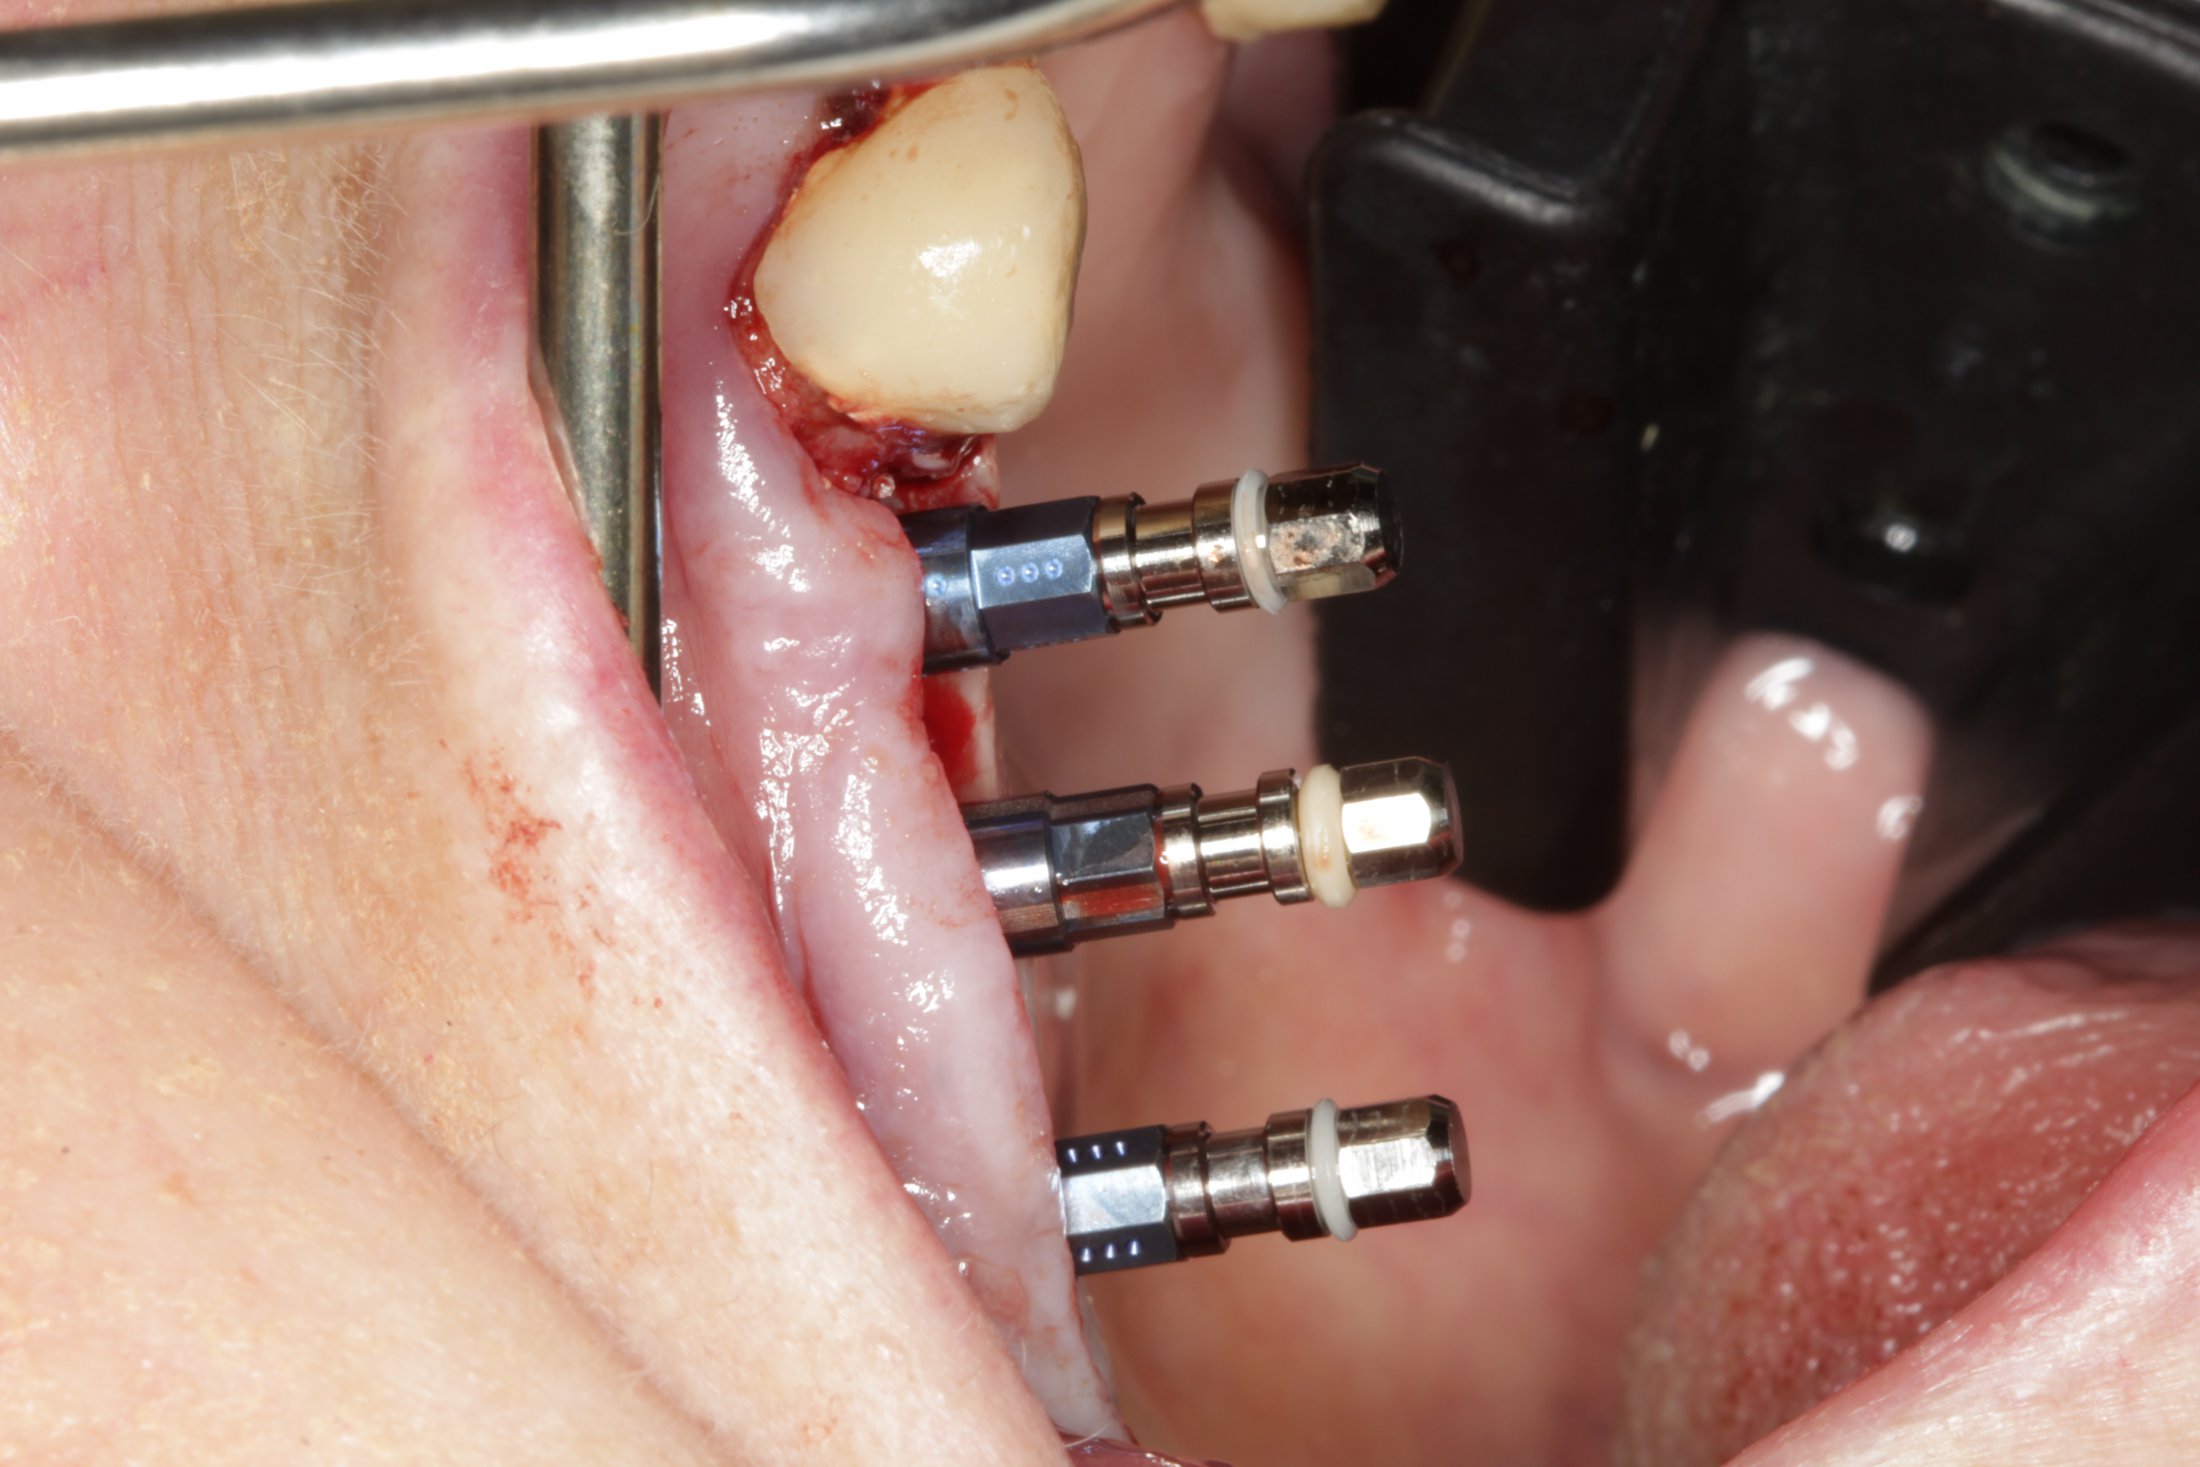

Your surgeon will cut the gum tissue where your back teeth used to be. The tissue is raised, exposing the bone. A small, oval window is opened in the bone. The membrane lining the sinus on the other side of the window separates your sinus from your jaw. This membrane is gently pushed up and away from your jaw.

Dr. Noroozi, certified periodontist in Burnaby, utilizes the most advanced technologies such as Piezosurgery to make your sinus lift surgery much safer, more effective and comfortable for you.

In the most common sinus augmentation procedure, a small incision is made on the premolar or molar region to expose the jaw bone. A small opening is cut into the bone, and the membrane lining the sinus is pushed upward. The underlying space is filled with bone grafting material, either from your own body or from a cadaver. Sometimes, synthetic materials that can imitate bone formation are used. After the bone is implanted, the incision is stitched up and the healing process begins.